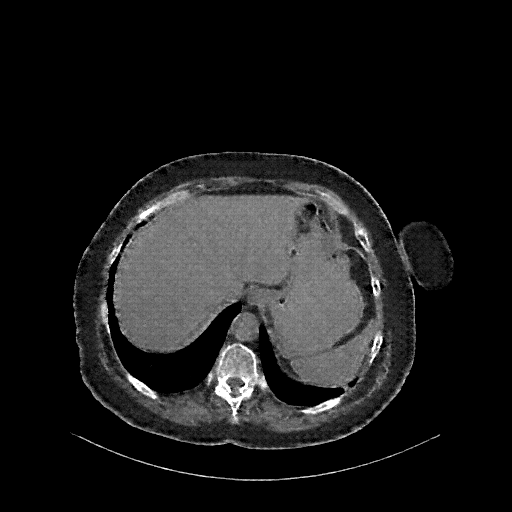

Generated VENOUS CT scan (A→B translation)

Full window (WL 1023.5, WW 4095 β†’ Low βˆ’1024, High +3071)

Lung window (WL -600, WW 1500 β†’ Low βˆ’1350, High +150)

Mediastinum window (WL 40, WW 400 β†’ Low βˆ’160, High +240)